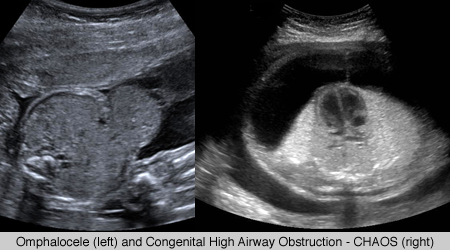

Pediatric Imaging

Dramatic advances in imaging technologies are improving the ability of pediatric radiologists to diagnose complex cases in children. For all imaging of children at UCSF we pay special attention to ensuring that protocols are pediatric specific and that all imaging studies are interpreted by radiologists who are specially trained in pediatric anatomy and pathology. UCSF ascribes to the policy of “imaging gently“[1] in the imaging of children, and the use of ultrasound is an important tool in achieving that goal.

UCSF’s ultrasound subspecialty has world-renowned experts in prenatal ultrasound imaging as well as for children and babies. Our expert staff includes specialists in prenatal imaging of congenital anomalies and fetal therapy.

Pediatric cranial sonogram.